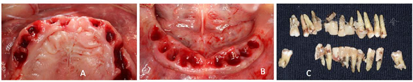

①阿替卡因肾上腺素注射液局部浸润麻醉,剪断固定结扎丝,拔除上下颌松动牙齿(图4)。暂保留了双侧下颌第三磨牙,主要考虑若下颌不能种植即刻修复情况下,利用38、48作为基牙辅助过渡可摘义齿固位。

牙周炎并非即刻种植的绝对禁忌证,系统综述表明彻底清除感染组织后,感染和健康的拔牙位点行即刻种植的种植体具有相似的种植体存活率[5]。有研究[6]认为重度牙周炎患者全口种植时机的选择应考量术前感染的控制难度,选择拔牙后择期种植能降低术前感染的控制难度,本例下颌因牙周感染较严重,术前和术中评估同期植入种植体失败风险较大,因此选择了拔牙后延期种植修复。

本例下颌左侧后牙区拔牙清创后,余留牙槽骨不足以支持种植体植入且获得良好的初期稳定性。因牙周病造成的骨吸收,下颌牙槽嵴严重萎缩,传统的可摘总义齿作为过渡义齿无法获得临床有效固位,利用右侧植入的种植体支持复合基台和球帽附着体制作过渡覆盖义齿[7],满足了患者下颌临时义齿应用的要求。上颌拔牙后通过即刻种植实现了早期固定修复。下颌拔牙术后的种植体支持可摘过渡总义齿修复,一方面满足了患者基本咀嚼功能,同时对上颌即刻种植固定义齿减小了咬合力。